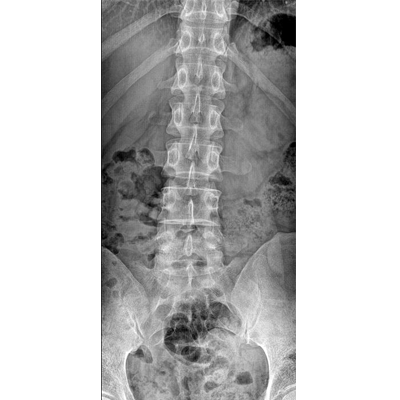

●探測(cè)器可以大范圍轉(zhuǎn)動(dòng),大尺寸有效探測(cè)面積,可滿足人體多部位攝影需求。